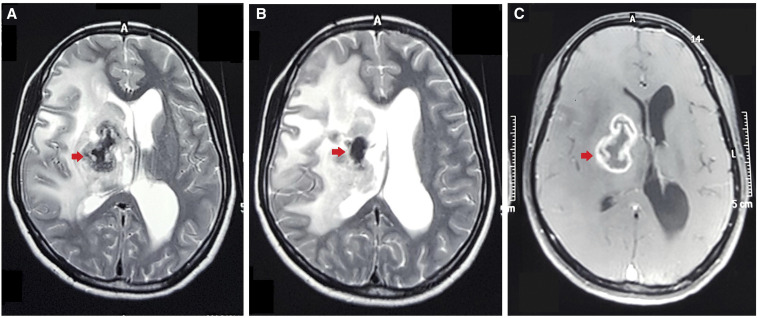

A 26-year-old woman with a low socioeconomic background living in rural northwest India presented with a longstanding headache that had worsened during the past 2 weeks and was associated with multiple episodes of vomiting and weakness on the left half of her body. Her past history did not suggest an immunocompromised state, comorbidities, or contact with tuberculosis. A general physical survey, including her nutritional status, was normal. Neurological examination revealed left hemiparesis and upper motor neuron facial paresis. Magnetic resonance imaging revealed a ring-enhancing lesion with perilesional edema in the basal ganglia and thalamic region (Figure 1C), along with a lipid peak on spectroscopy. The center of the lesion was markedly hypointense on T2-weighted imaging, suggesting caseous necrosis (Figure 1A, B). The typical appearance suggested a tuberculoma, which was confirmed with stereotactic biopsy.

Figure 1.

(A, B) Tuberculoma in the right basal ganglia with markedly hypointense center (arrow) in T2-weighted magnetic resonance imaging and (C) ring enhancement on contrast administration. This figure appears in color at www.ajtmh.org.